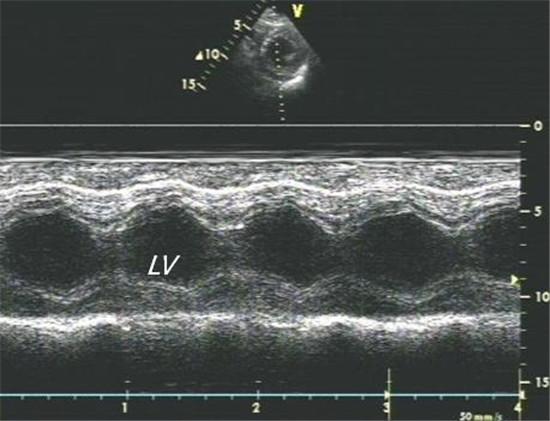

正常超声心动图

正常超声心动图,超声心动图正常值

(m型超声心动图左室短轴切面显示心肌收缩运动较正常稍有增强)

m型超声心动图